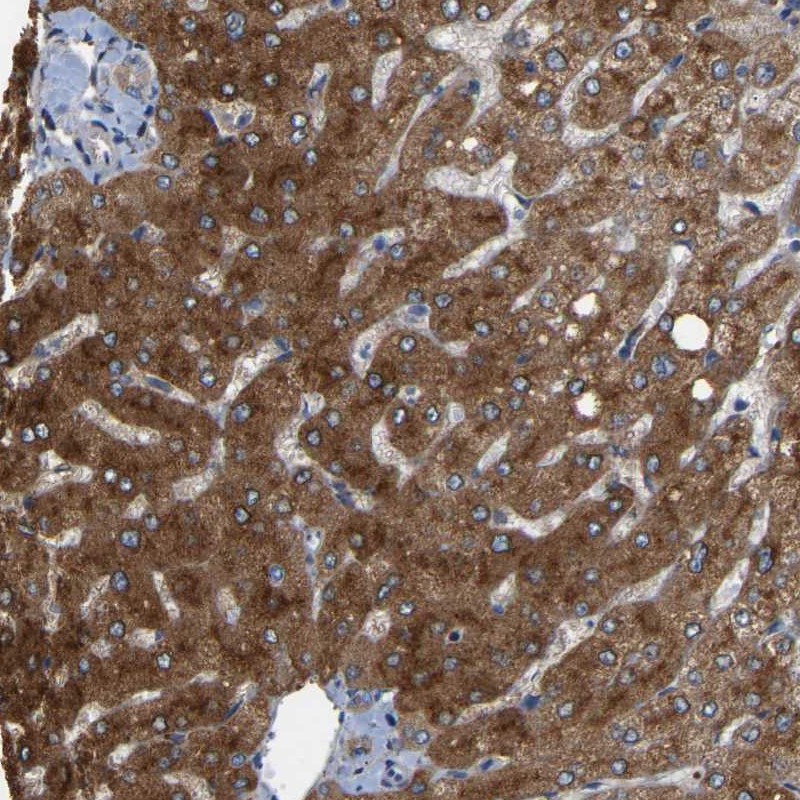

Immunohistochemical staining of human liver shows strong cytoplasmic positivity in hepatocytes.